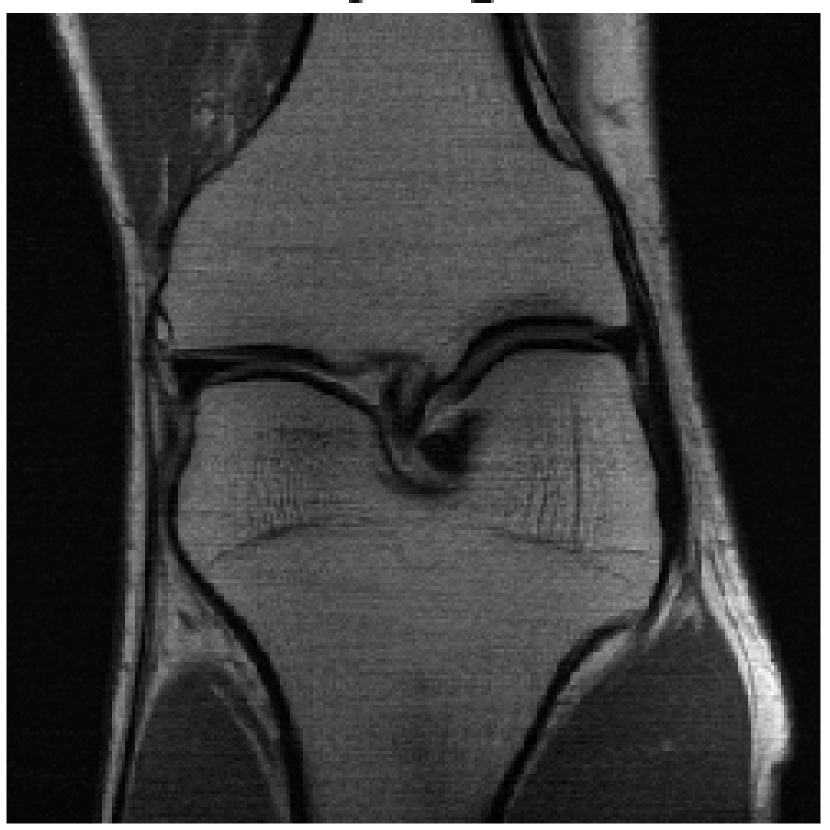

We evaluated our models on three data sets: the validation set as in Zbontar et al. (2018), and the test and challenge sets through the fastMRI website. A summary of these evaluations can be found in table 1111Results on the challenge data set will be added once publicly available.. To assess image quality more closely, we show some exemplary reconstructions from each model in figure 1.

(d) Single-Coil ESC

Ground Truth

Refer to caption

Figure 1: Example reconstructions. The reconstructions visually improve the ground truth images, suggesting a strong prior.